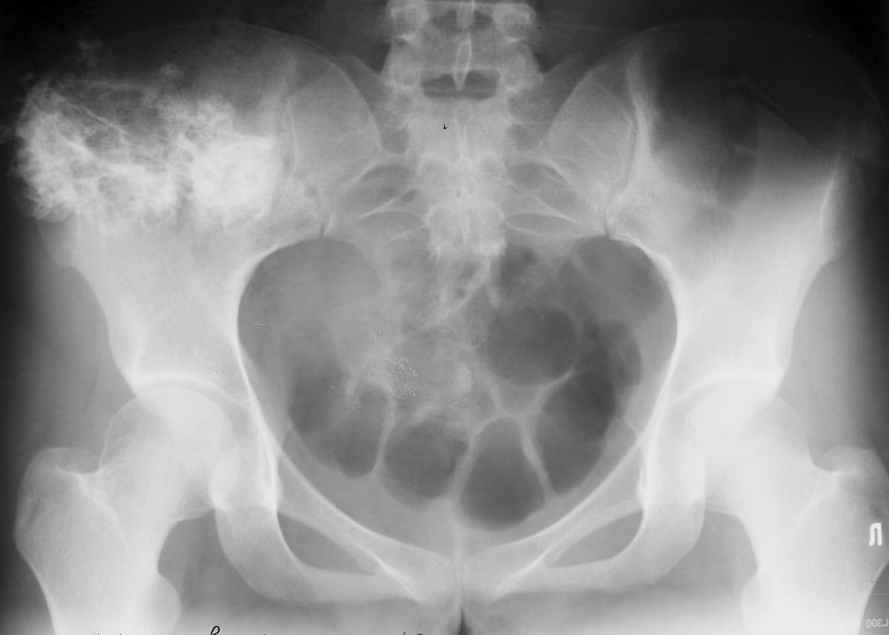

Уважаемые коллеги! К нам поступила пациентка 16 лет с диагнозом: остеохондрома крыла правой подвздошной кости.

Учитывая большие размеры образования, необходимо удаление его с резекцией крыла подздошной кости вместе с ее гребнем. Предполагается наличие большого дефекта. Поделитесь опытом закрытия таких дефектов.

По-моему, КТ-картина наводит на мысль об озлокачествлении (резкая неоднородность, местами размытие контуров) - вторичной хондросаркоме. Местами, кстати, имеется рост и в направлении брюшной полости. Для решения вопроса об объеме резекции в данном случае оправдана трепанобиопсия. Если это хондросаркома, особенно низкодифференцированная, то стоит обсудить возможность удаления всего крыла с окружающими мягкими тканями. Вариант реконструкции - комбинированная пластика аллотрансплантатами. А вот какими - зависит от наличия костного банка и возможностью индивидуального изготовления трансплантатов. При отсутствии таковой не лучше ли направить ее в ЦИТО?

Получены результаты гистологического исследования.Процесс доброкачественный. Диагноз хондрома крыла таза подтвержден.Вопрос: чем и как закрыть предполагаемый значительный дефект крыла?

Уважаемые коллеги, больную прооперировали. После выделения остеохондрома резецирована в пределах неизменённой кости. Выявлено, что гребень подвздошой кости не пострадал от опухоли. В результате резекции сформирован сквозной дефект в крыле подвздошной кости треугольной формы 6х7х8 см. В качестве трансплантата использована наружная кортикальная пластинка заднего отдела крыла подвздошной кости.

Трансплантат фиксирован на месте дефекта при помощи шурупов и проволоки. Кровопотеря 550 мл.